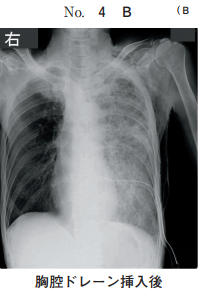

44 64 歳の男性。呼吸困難を主訴に来院した。日前に左胸痛と息切れとが出現し、 次第に増悪してきたため受診した。体温 36.2 ℃。脈拍 100/分、整。血圧 120/80 mmHg。呼吸数 20/分。SpO2 92 %room air 。眼瞼結膜と眼球結膜とに異常を認 めない。頸部リンパ節を触知しない。左胸部に呼吸音を聴取しない。血液所見赤 血球 420 万、Hb 13.0 g/dl、Ht 37 %、白血球 4,400桿状核好中球%、分葉核好 中球 60 %、好酸球%、好塩基球%、単球%、リンパ球 25 % 、血小板 21 万。 CRP 0.4 mg/dl。来院時の胸部エックス線写真別冊No. 4 を別に示す。入院後、 胸腔ドレーンを挿入したところ、直後から咳嗽と泡沫状の喀痰とが出現した。この 時点の胸部エックス線写真別冊No. 4 を別に示す。 胸腔ドレーン挿入後の病態として正しいのはどれか。

(A) 肺 炎 (B) 肺水腫 (C) 無気肺 (D) 肺胞出血 (E) うっ血性心不全